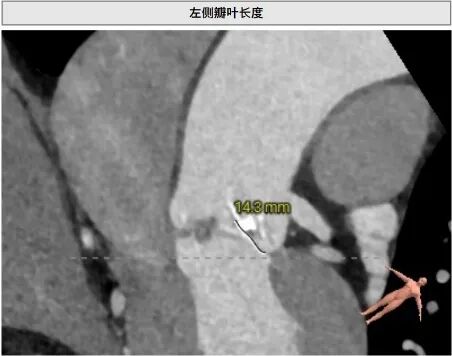

手术风险、难点

患者左冠脉开口高度11.0mm,左冠窦瓣叶长度14.3mm, 瓣叶明显增厚,有轻度钙化。应注意术中有冠脉闭塞风险。患者未见明显心室隔膜部,新发的房室传导阻滞风险较高。